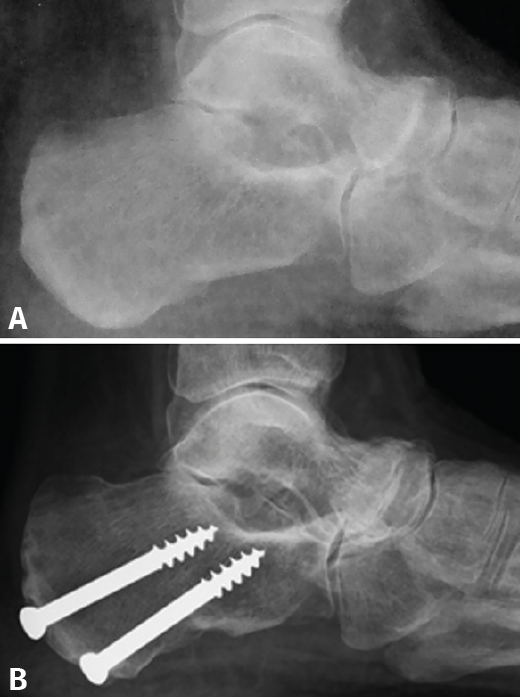

Resultados: todos los pacientes tenían un varo subtalar y el 88,2% una fórmula metatarsal index minus. Existió una mejoría en todas las escalas de valoración utilizadas y en los parámetros radiológicos estudiados (cobertura talonavicular y clasificación de Maceira) en la mayoría de los pacientes. No se registraron complicaciones importantes. Un paciente no mejoró y precisó de una artrodesis a los 4 años de la osteotomía.

Conclusiones: la EMW produce un pie plano paradójico. La corrección quirúrgica del varo subtalar permite una mejoría clínica y radiológica notable. La osteotomía “supervalguizante” es una técnica sencilla y se ha constituido en nuestra técnica de elección, independientemente del estadio radiológico. La artrodesis de la columna medial ha quedado como técnica de rescate para fracasos de la cirugía de preservación articular.

Results: all patients presented with subtalar varus and 88.2% had a metatarsal index minus formula. There was an improvement in all scales studied. Radiographic parameters also improved in all cases (talonavicular coverage, Maceira classification). Most patients had considerable pain relief and just one did not improve and required an arthrodesis four years after the osteotomy.

Conclusion: MWD presents with a paradoxical flatfoot varus. Surgical correction of hindfoot varus allows for a mechanical change that produces clinical and radiological improvement. An isolated “super-lateral-slide osteotomy” is an easy technique to achieve varus correction regardless the radiographic stage of the disease and has become our surgical procedure of choice. Medial column arthrodesis is left as a salvage procedure for those cases that do not improve with the osteotomy.